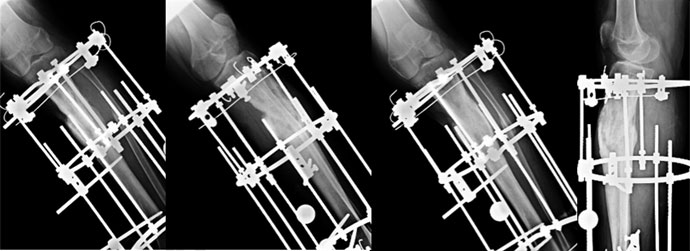

| 2 months |

| 2 months on, he continues to improve. The x-rays show signs of healing. There is formation of bridging callus. |

| 4 months post surgery – before fixator removal |

| At 4 months the fracture is healed. The callus is well consolidated. The fixator was then removed after gradual disassembly. |